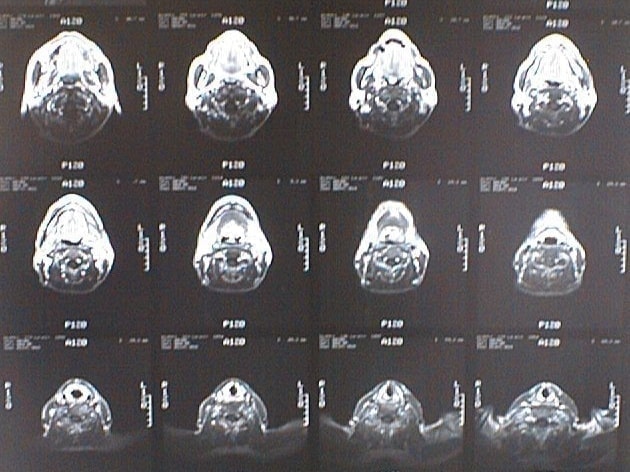

CT画像比較

中咽頭末期がんCT画像①

入院当時CT画像①

中咽頭末期がん消滅CT画像①

入院3か月後癌消滅CT画像①

中咽頭末期がんCT画像②

入院当時CT画像②

中咽頭末期がん消滅CT画像②

入院3か月後癌消滅CT画像②

中咽頭末期がんCT画像③

入院当時CT画像③

中咽頭末期がん消滅CT画像③

入院3か月後癌消滅CT画像③